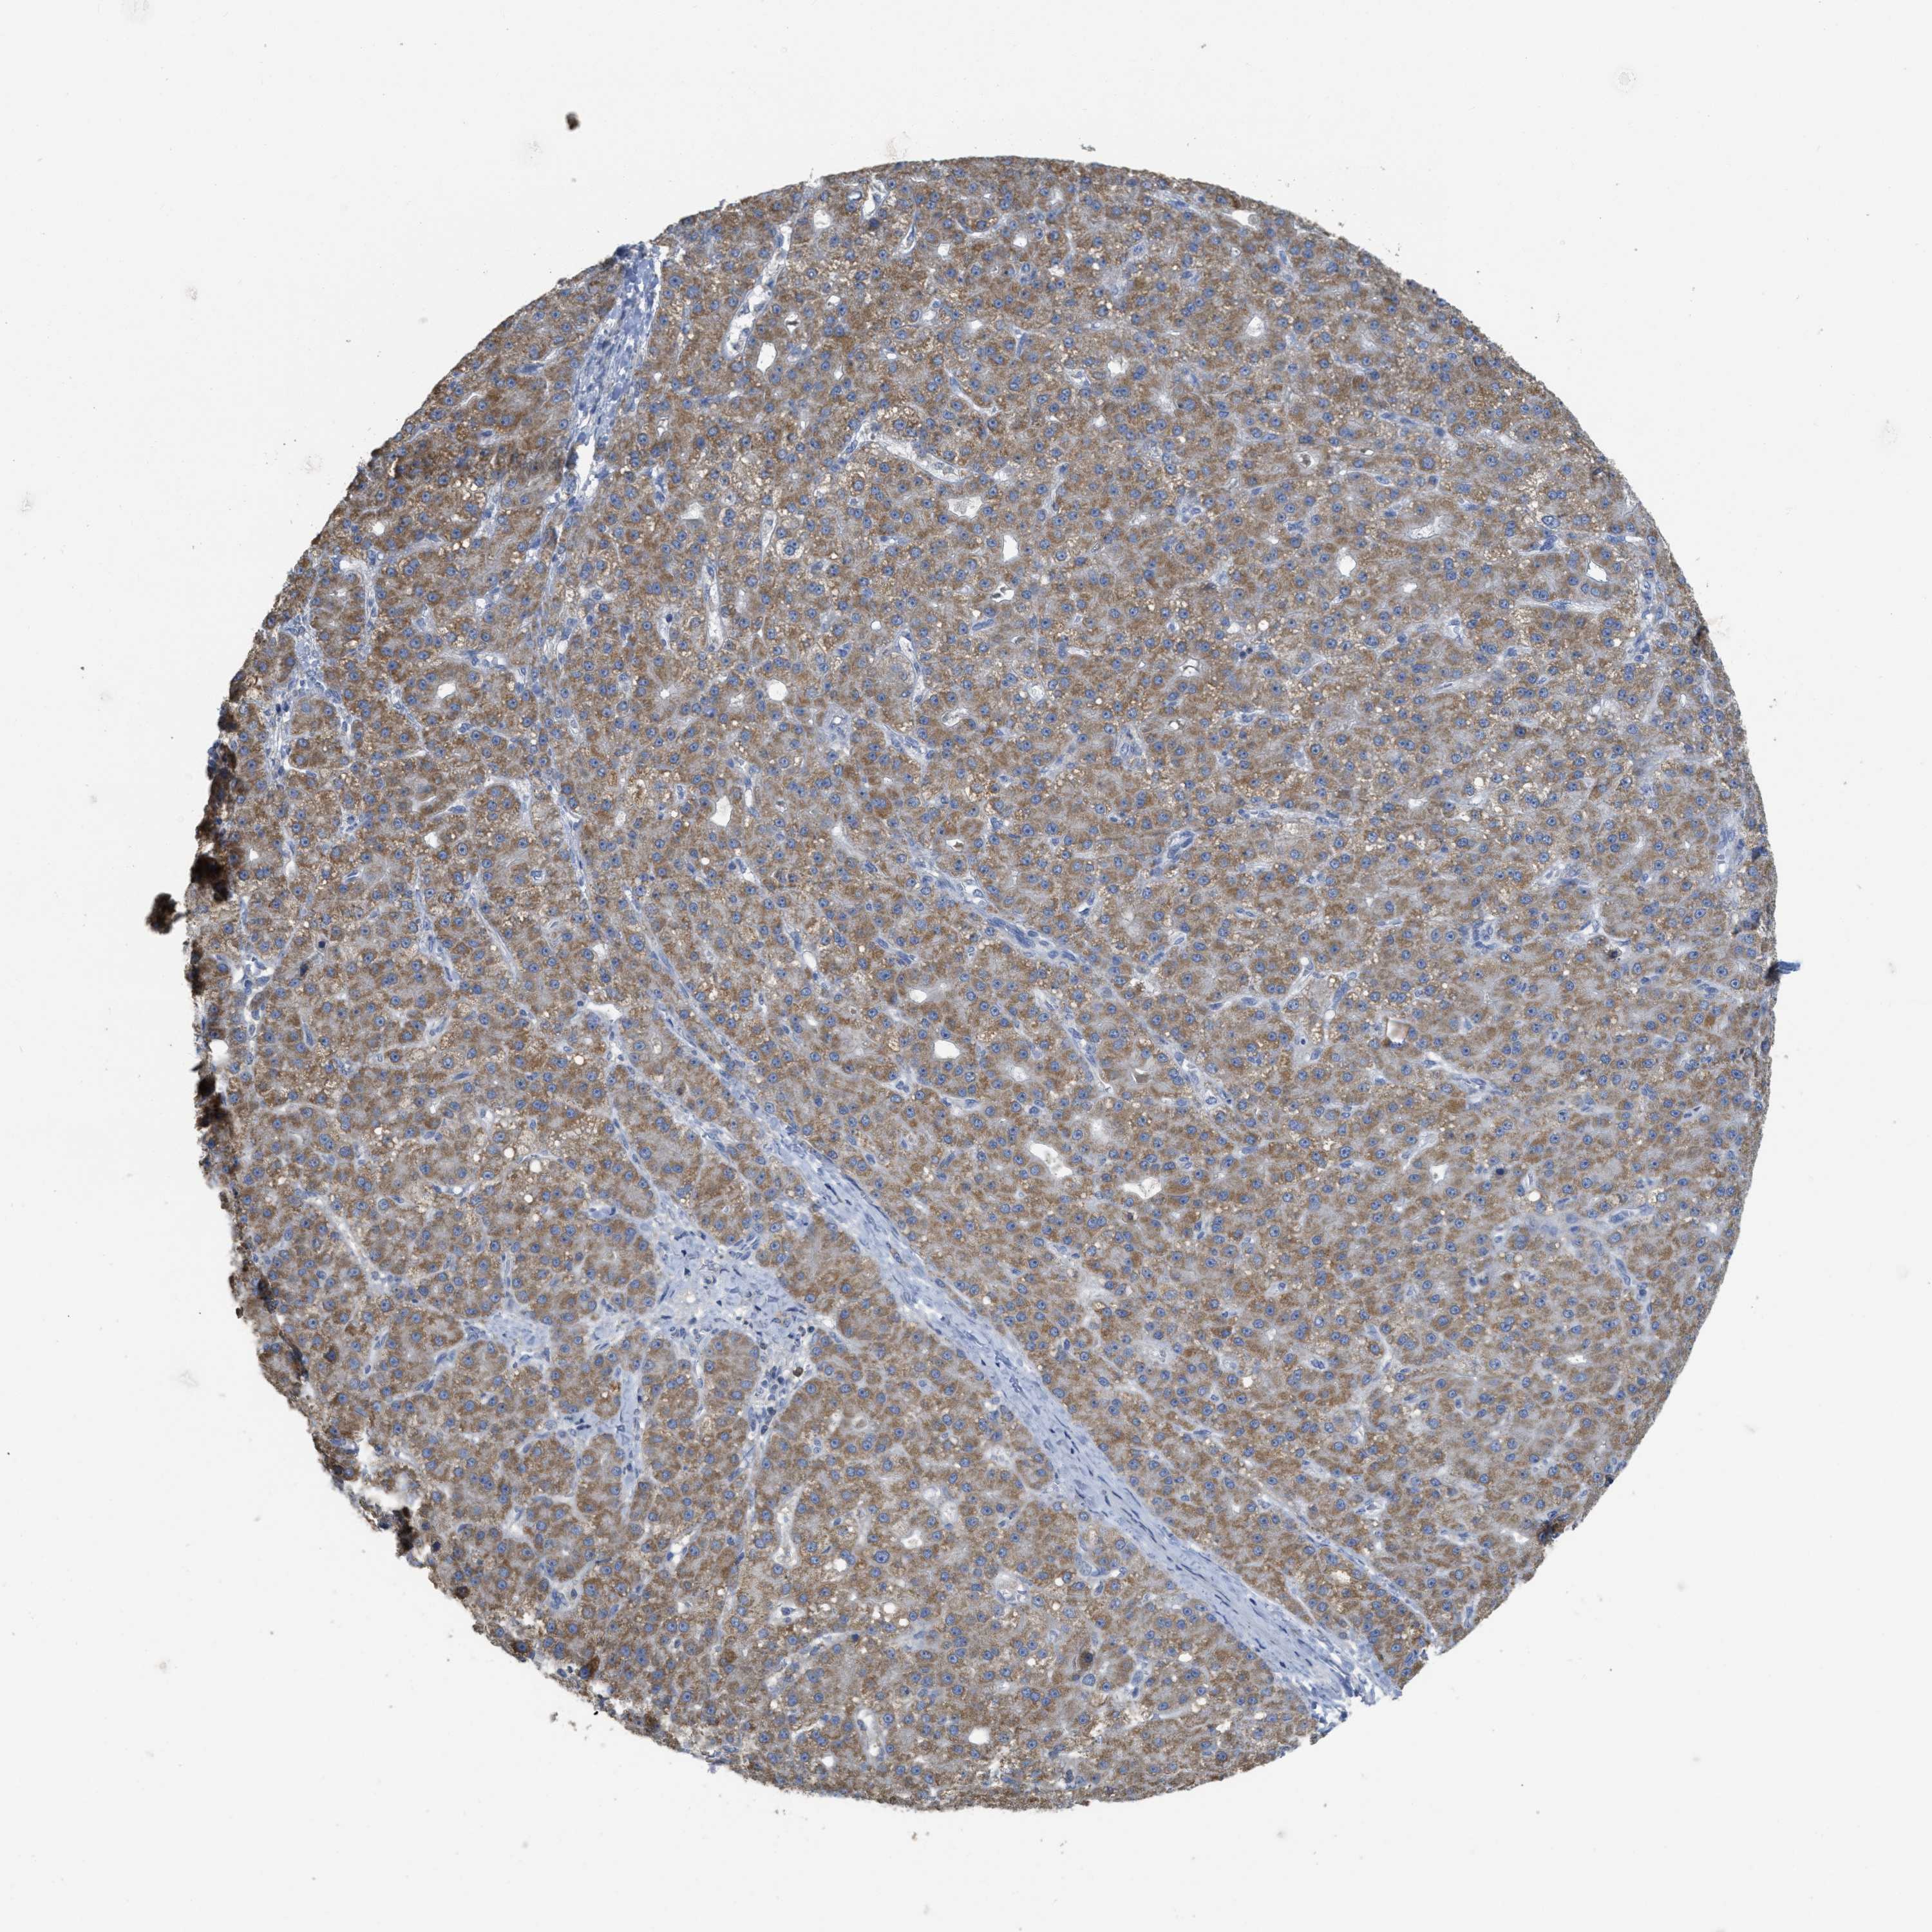

LIVER CANCER - Protein expressioni

A mouse-over function shows sample information and annotation data. Click on an image to view it in a full screen mode. Samples can be filtered based on level of antibody staining by selecting one or several of the following categories: high, medium, low and not detected. The assay and annotation is described here.

Note that samples used for immunohistochemistry by the Human Protein Atlas do not correspond to samples in the TCGA dataset.

Antibody stainingi

Antibody staining in the annotated cell types in the current human tissue is reported as not detected, low, medium, or high, based on conventional immunohistochemistry profiling in selected tissues. This score is based on the combination of the staining intensity and fraction of stained cells.

Each image is clickable and will lead to virtual microscopy that enables deeper exploration of all samples and also displays staining intensity scores, fraction scores and subcellular localization as well as patient and tissue information for each sample.

Antibody HPA018150

Antibody HPA026834

Staining

High

Medium

Low

Not detected

Intensity

Strong

Moderate

Weak

Negative

Quantity

>75%

75%-25%

<25%

None

Location

Nuclear

Cytoplasmic/membranous

Cytoplasmic/membranous,nuclear

Cholangiocarcinoma

Carcinoma, Hepatocellular, NOS